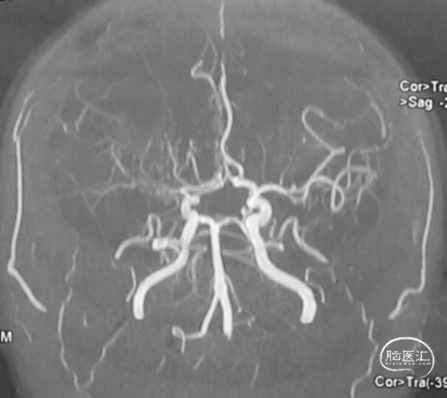

病人甲的影像资料:

T2 Flair:左侧额顶叶脑软化灶,右侧内分水岭区腔梗;

弥散:阴性;

MRA:右侧大脑前动脉、大脑中动脉闭塞,左侧大脑中动脉分支减少;

造影:右侧颈内动脉末端变细,大脑前及大脑中自起始部闭塞,脑底少量烟雾血管形成,汇聚使R-MCA少量分支显影。

总结:30年前左侧大脑中动脉分支闭塞,导致左侧额顶叶脑梗塞,遗留右上肢肌力差。本次为右侧大脑中动脉闭塞导致的内分水岭梗塞症状。